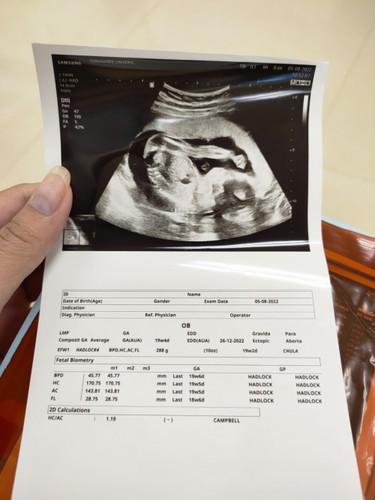

บ้านนี้ 21 5weekแล้วค่ะ ดิ้นดี ดิ้นเก่ง ไม่มีวันที่ไม่ดิ้น 55555 ภาพตอนไปซาวด์ 20 3weekค่ะ น้องผู้หญิง น้องดิ้นตั้งแต่นั่งรอจนเข้าห้องก็ดิ้นไม่หยุด

ถาพอัลตราซาว แม่ จขพ. ชัดจังเลยคะ

ต้องขอบคุณคุณหมอค่ะ กว่าจะหามุมได้